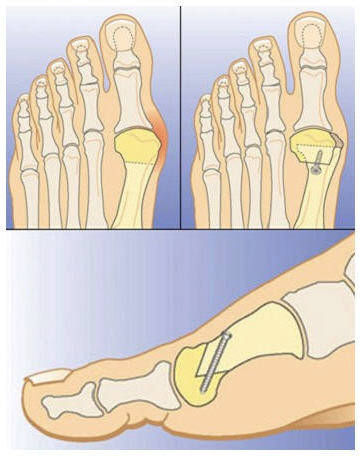

Медицинские решения: Операция по коррекции Hallux valgus